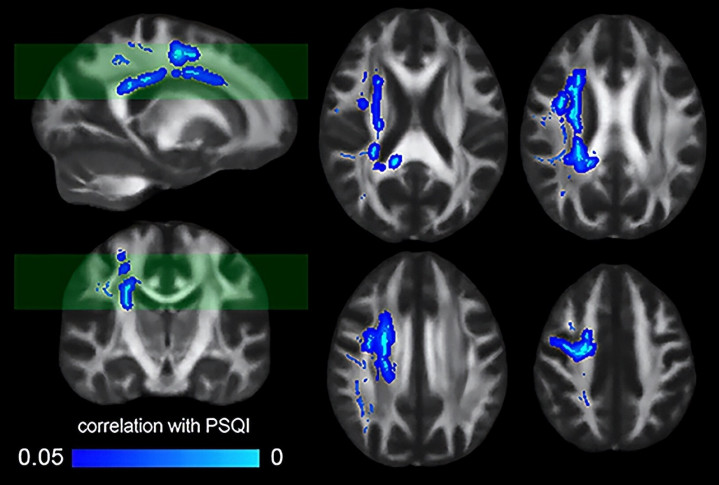

研究人员将人脑白质结构与参与者的匹兹堡睡眠质量指数(PSQI)评分进行了比较。(Simayi等人,《美国国家科学院院刊》,2026)

研究团队还分析了185名健康志愿者的核磁共振(MRI)扫描数据。

结果显示,那些自我报告睡眠质量较差的参与者,其大脑白质的结构完整性也相对较差。

白质主要由被髓鞘包裹的神经纤维组成,这一发现将动物实验的结论与人类的脑部健康紧密地联系在了一起。

它有力地证明,无论是在啮齿动物还是人类身上,睡眠与大脑微观结构的完整性都息息相关。